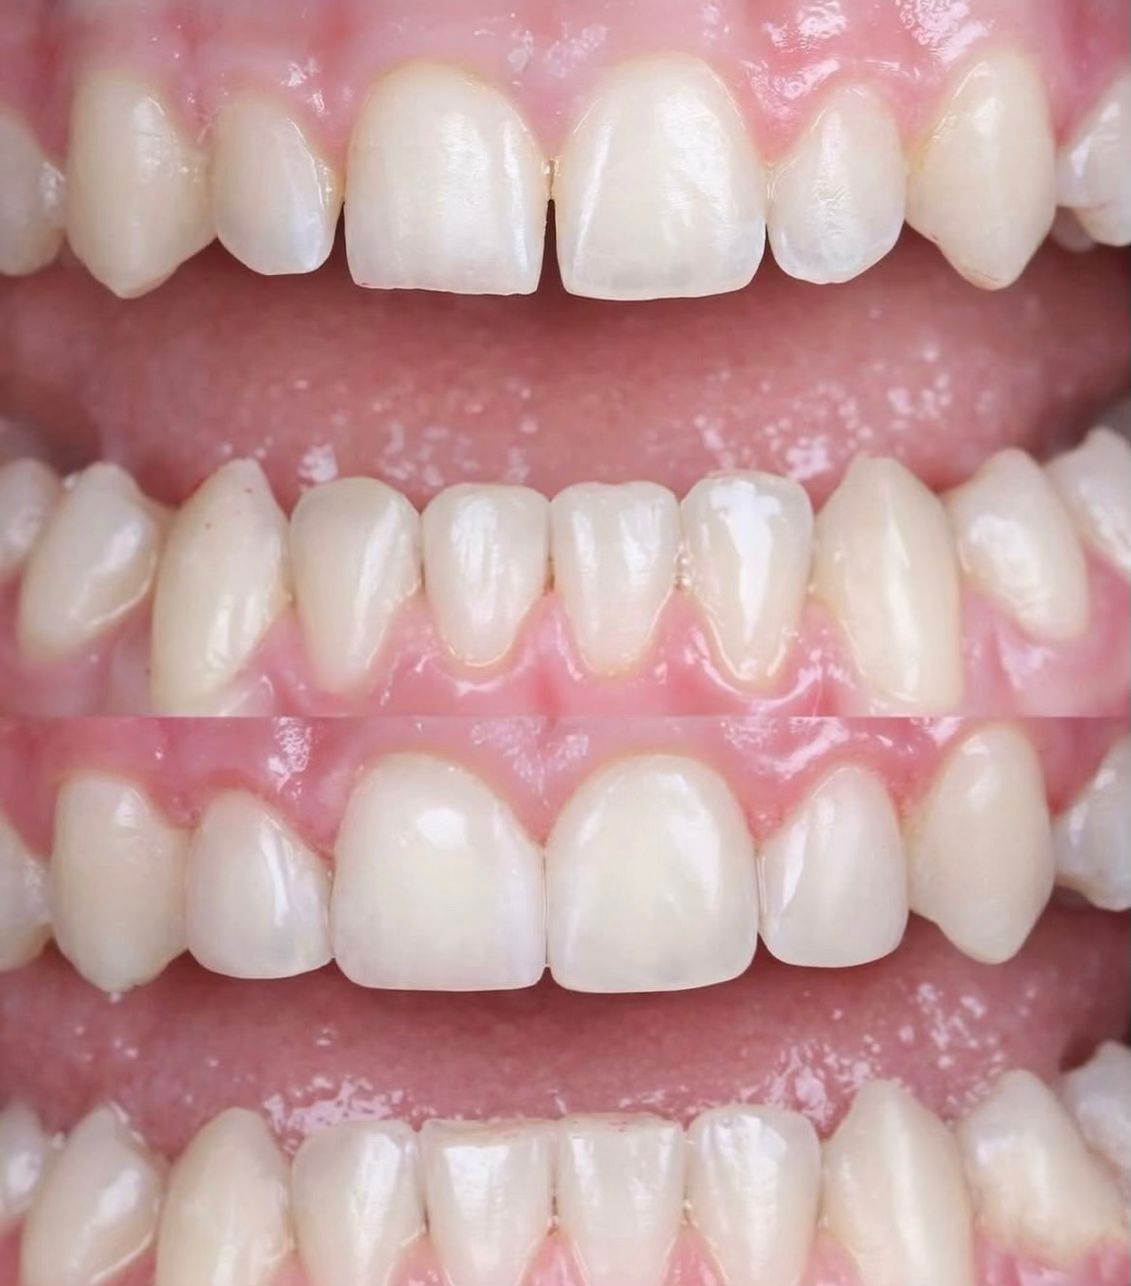

Zirkonyum kaplama

Zirkonyum kaplama, estetik ve dayanıklılığı bir arada sunan modern bir porselen kaplama yöntemidir. Işık geçirgenliği sayesinde doğal diş görünümüne en yakın sonucu verirken, sağlam yapısıyla uzun yıllar güvenle kullanılabilir.

Metal altyapı içermediği için diş eti uyumu yüksektir ve zamanla oluşabilecek gri yansımalara neden olmaz. Özellikle ön diş estetiğinde doğal ve beyaz bir görünüm isteyen hastalar için ideal bir çözümdür. Sağlam altyapı, doğal görünüm ve özgüvenli bir gülüş için zirkonyum kaplama ideal bir tercihtir.